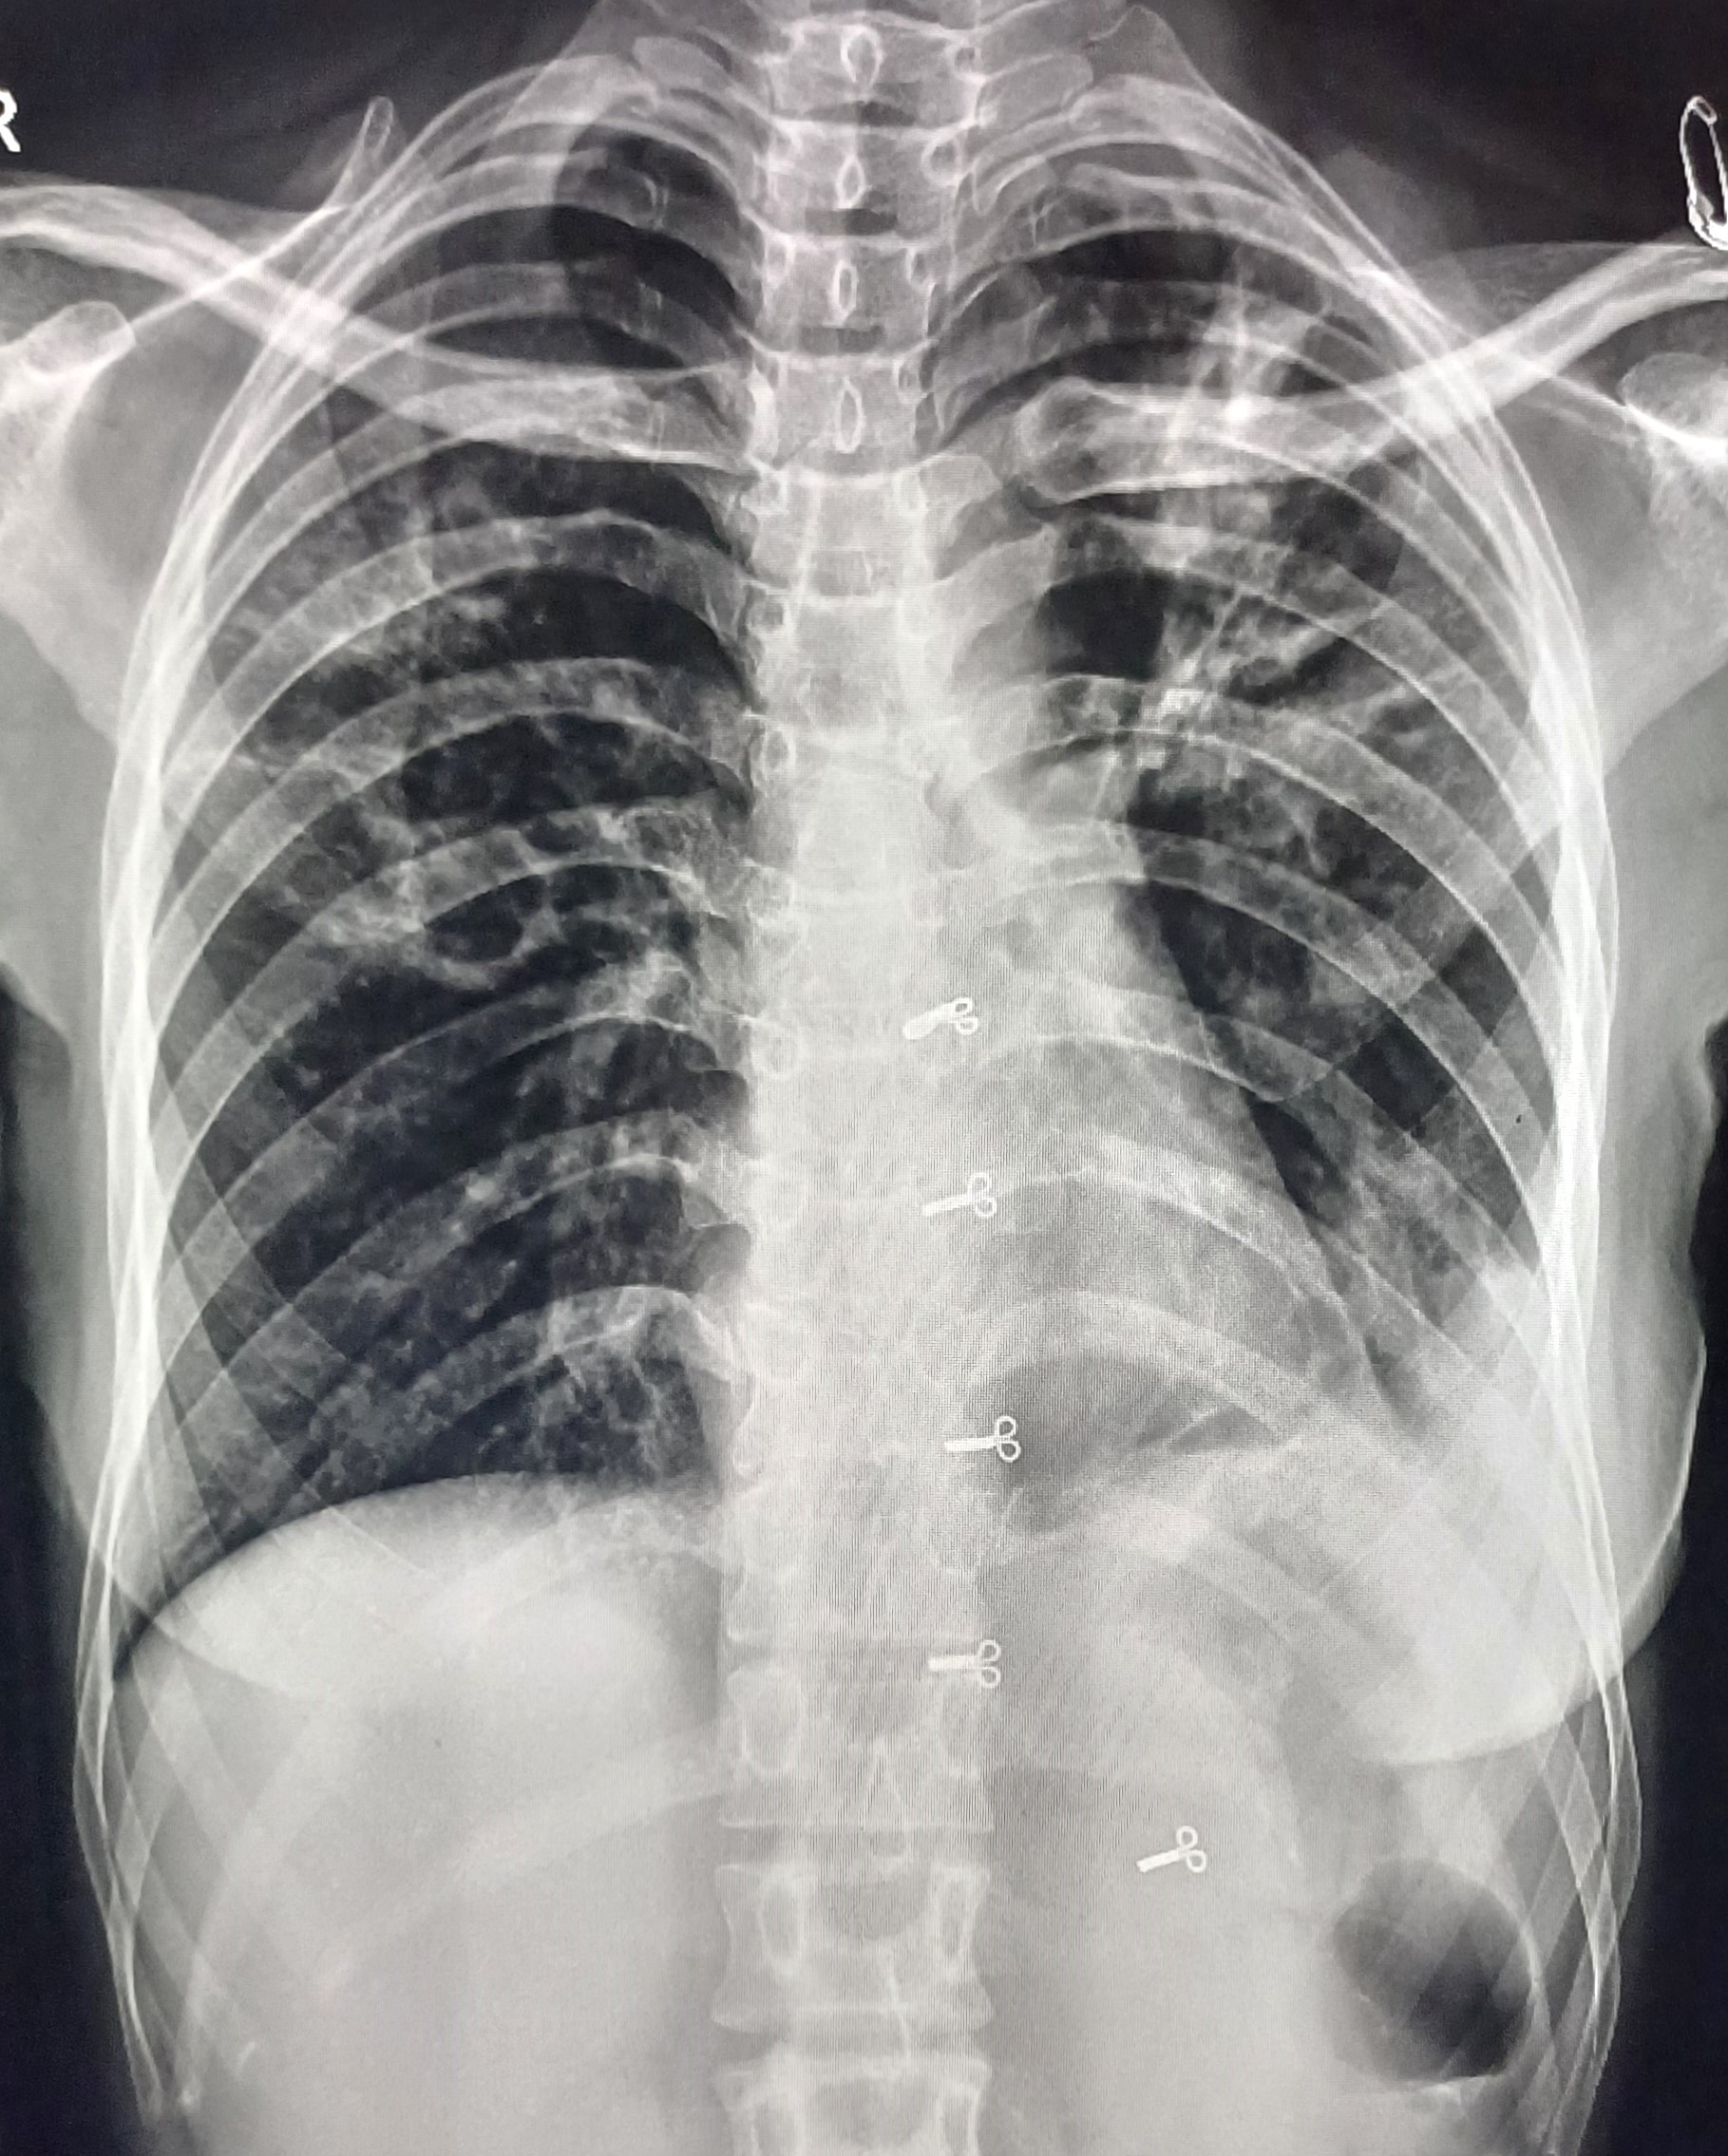

| 50 | IGGMC, Nagpur, Nagpur | P2 | 29-4422 | Shakuntalabai Paradkar | Consent taken on Paper | 83 Yrs. |

Provisional Diag : Post TB Sequelae With Reactivation?

Final Diag : Post TB Sequelae |

Post TB Sequelae | Fibrotic Lesion Present, left Sided tracheal Pull Present, Left Upper Zone Old Heald Calcified Lesion Present, Right Upper, Mid & Lower Zone Infiltration Present | Abnormality visible on x-ray |

View |